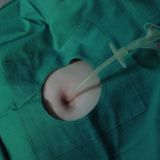

Enfermedades relacionadas con el recto-ano

-

Hemorroides internas

Fisura anal

Cáncer de recto

Cáncer anal